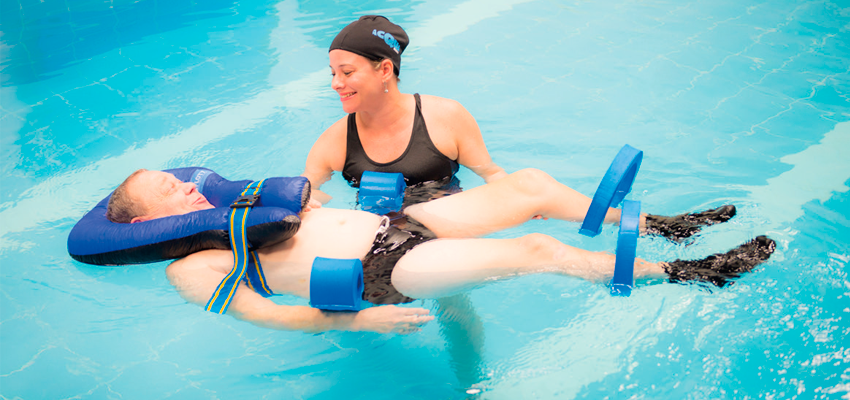

Natação e hidroterapia

Muitos efeitos terapêuticos benéficos obtidos com a imersão na água aquecida (como o relaxamento, a analgesia, a redução do impacto e da agressão sobre as articulações) são associados aos efeitos possíveis de se obter com os exercícios realizados quando se exploram as diferentes propriedades físicas da água.